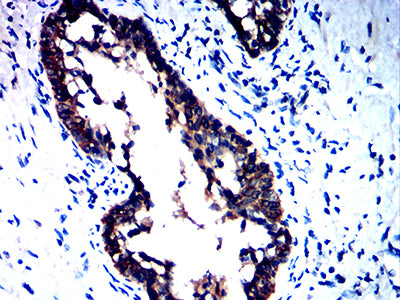

Immunohistochemical analysis of paraffin-embedded human ovarian cancer tissues using CD258 mouse mAb with DAB staining.

-

Immunohistochemical analysis of paraffin-embedded human prostate cancer tissues using CD258 mouse mAb with DAB staining.